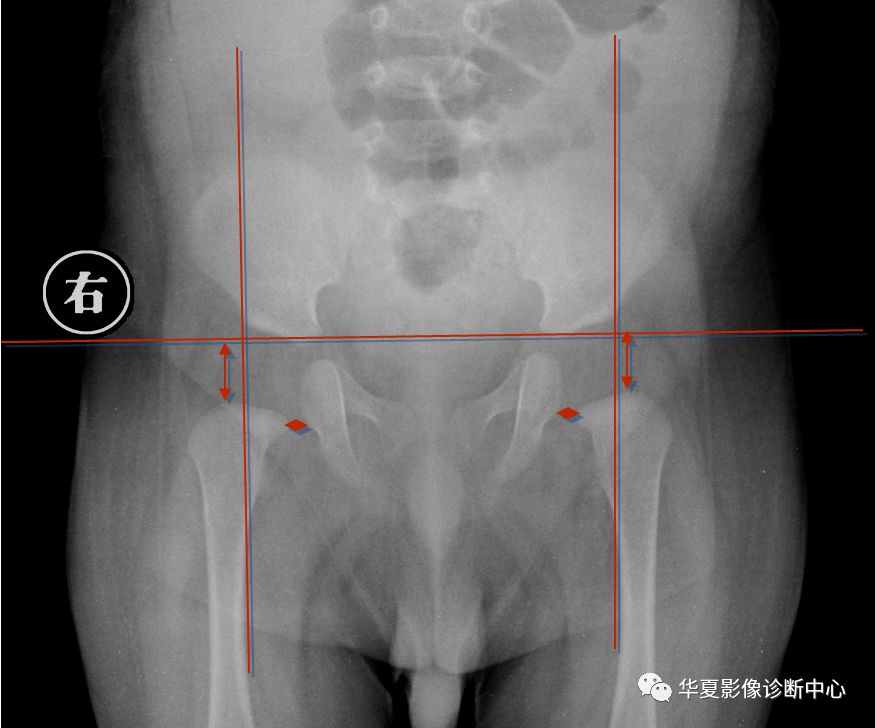

2.骨盆平片测量法

如图所示两侧髋臼Y形软骨连成为Hilg-eneriner线,简称为H线,股骨上端距H线之距离为上方间隙。股骨上端鸟嘴距坐骨支外缘为内侧间隙,正常均值上方间隙为9.5mm,内侧间隙为4.3mm。若上方间隙小于8.5mm,内侧间隙大于5.1mm应怀疑髋关节脱位。若上方间隙小于7.5mm,内侧间隙大于6.1mm可诊断为髋关节脱位,此法简易可靠。

3.Perkin象限

当股骨头骨骺核出现后可利用Perkin象限,即两侧髋臼中心连一直线称为H线,再从髋臼外缘向H线做一垂线(P),将髋关节划分为四个象限,正常股骨头骨骺位于内下象限内。若在外下象限为半脱位,在外上象限为全脱位。

新生儿正常股骨上端鸟嘴状突起位于内下象限内。若在外下象限为半脱位,在外上象限为全脱位。

股骨头预测骨骺法

即以股骨颈上缘为底边,作一等边三角形,三角形顶点为预测股骨头骨骺,再结合Perkin方格法判断。